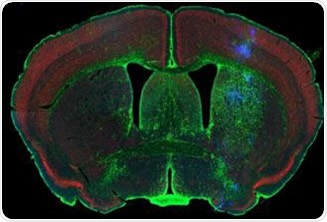

Figure 1. Rodent brain (top) depicting simultaneous acquisition of fluorophores Cy2, Cy3 and Cy5; Brain image (bottom) magnified to 0.5 μm. Image credit: Huron Digital Pathology.

- This is the only confocal fluorescence digital slide scanner that enables the simultaneous acquisition of up to three fluorophores spanning the whole visible spectrum, from 400nm-850nm. This provides considerable time-savings and less photo bleaching due to the unique flying-spot laser platform.